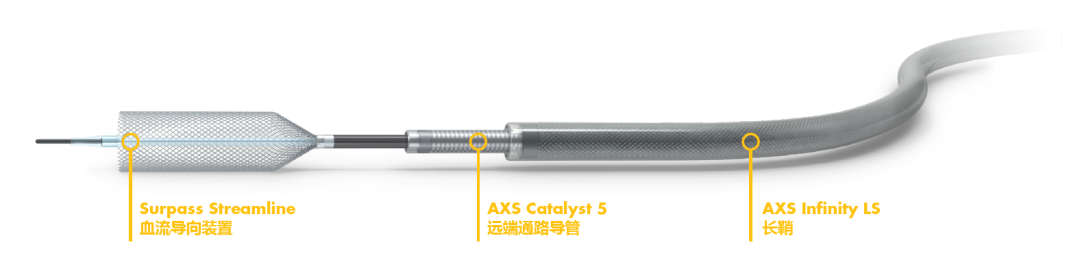

单纯血流导向装置置入,对于远期动脉瘤整体缩小具有积极作用。对狭窄应该进行球囊预扩张,防止支架打不开,但是也存在一个疑虑,万一是血栓生长导致管腔丢失,那么扩张有可能引起血栓破碎,有导致远端栓塞事件的风险。整个病变较长,同时远近端血管直径存在差别,首选Surpass Streamline,因为它可以选用最长50cm的型号,一个支架可以解决问题,同时径向支撑力大,对于狭窄后续恢复有帮助。

方案确定后,充分双抗,全麻下进行手术,常规长鞘,置入Cat5。手术中间一个小的细节告诉我们这是一个巨大动脉瘤,内部血栓是新鲜的。应用Cat5做路图的时候,能够看到造影剂进入到血栓内部,勾勒出动脉瘤的大小,同时提示血栓是松动的。除了病变段血管,患者其它血管状态还是很不错的。XT-27到位很容易,尝试着不扩张狭窄,直接跟进Cat5,发现中间导管很容易通过病变近端狭窄段,这说明它不是动脉硬化性的坚硬狭窄。因而,立即调整手术策略,取消球囊预扩张,直接通过中间导管。和设想的一样,Cat5轻松到达大脑中动脉。选择了4mm*40mm的支架,送入过程是顺利的,锚定支架远端位置之后,缓慢释放,推的力量下,可以看到支架顺利张开,即使在狭窄的部位也能看到支架完全打开。最终完美释放,即刻造影显示血管完全修复至正常状态,动脉瘤内造影剂进入明显减少。双容积重建显示支架贴壁良好。